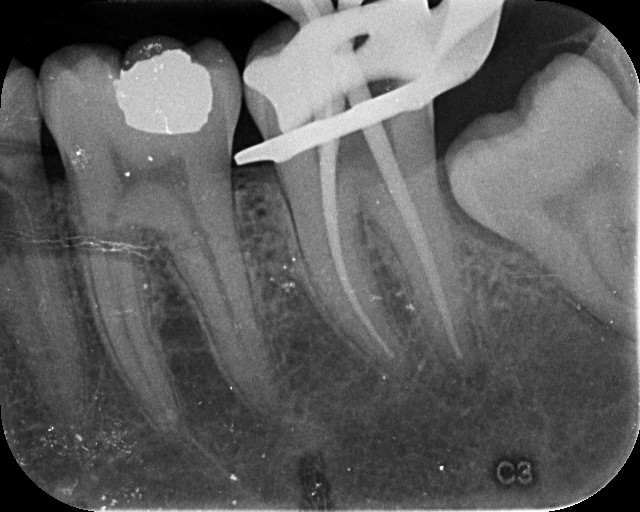

At Microsmiles, every root canal is performed under a high-resolution dental microscope, allowing our specialists to treat even the most complex canals with pinpoint accuracy. This level of detail isn’t just high-tech-it leads to faster treatment, fewer appointments, and long-lasting results.

Our microscope-enhanced approach ensures we do things right the first time-minimizing the need for return visits or repeat procedures. That means you spend less time in the dental chair, and more time doing what you love.